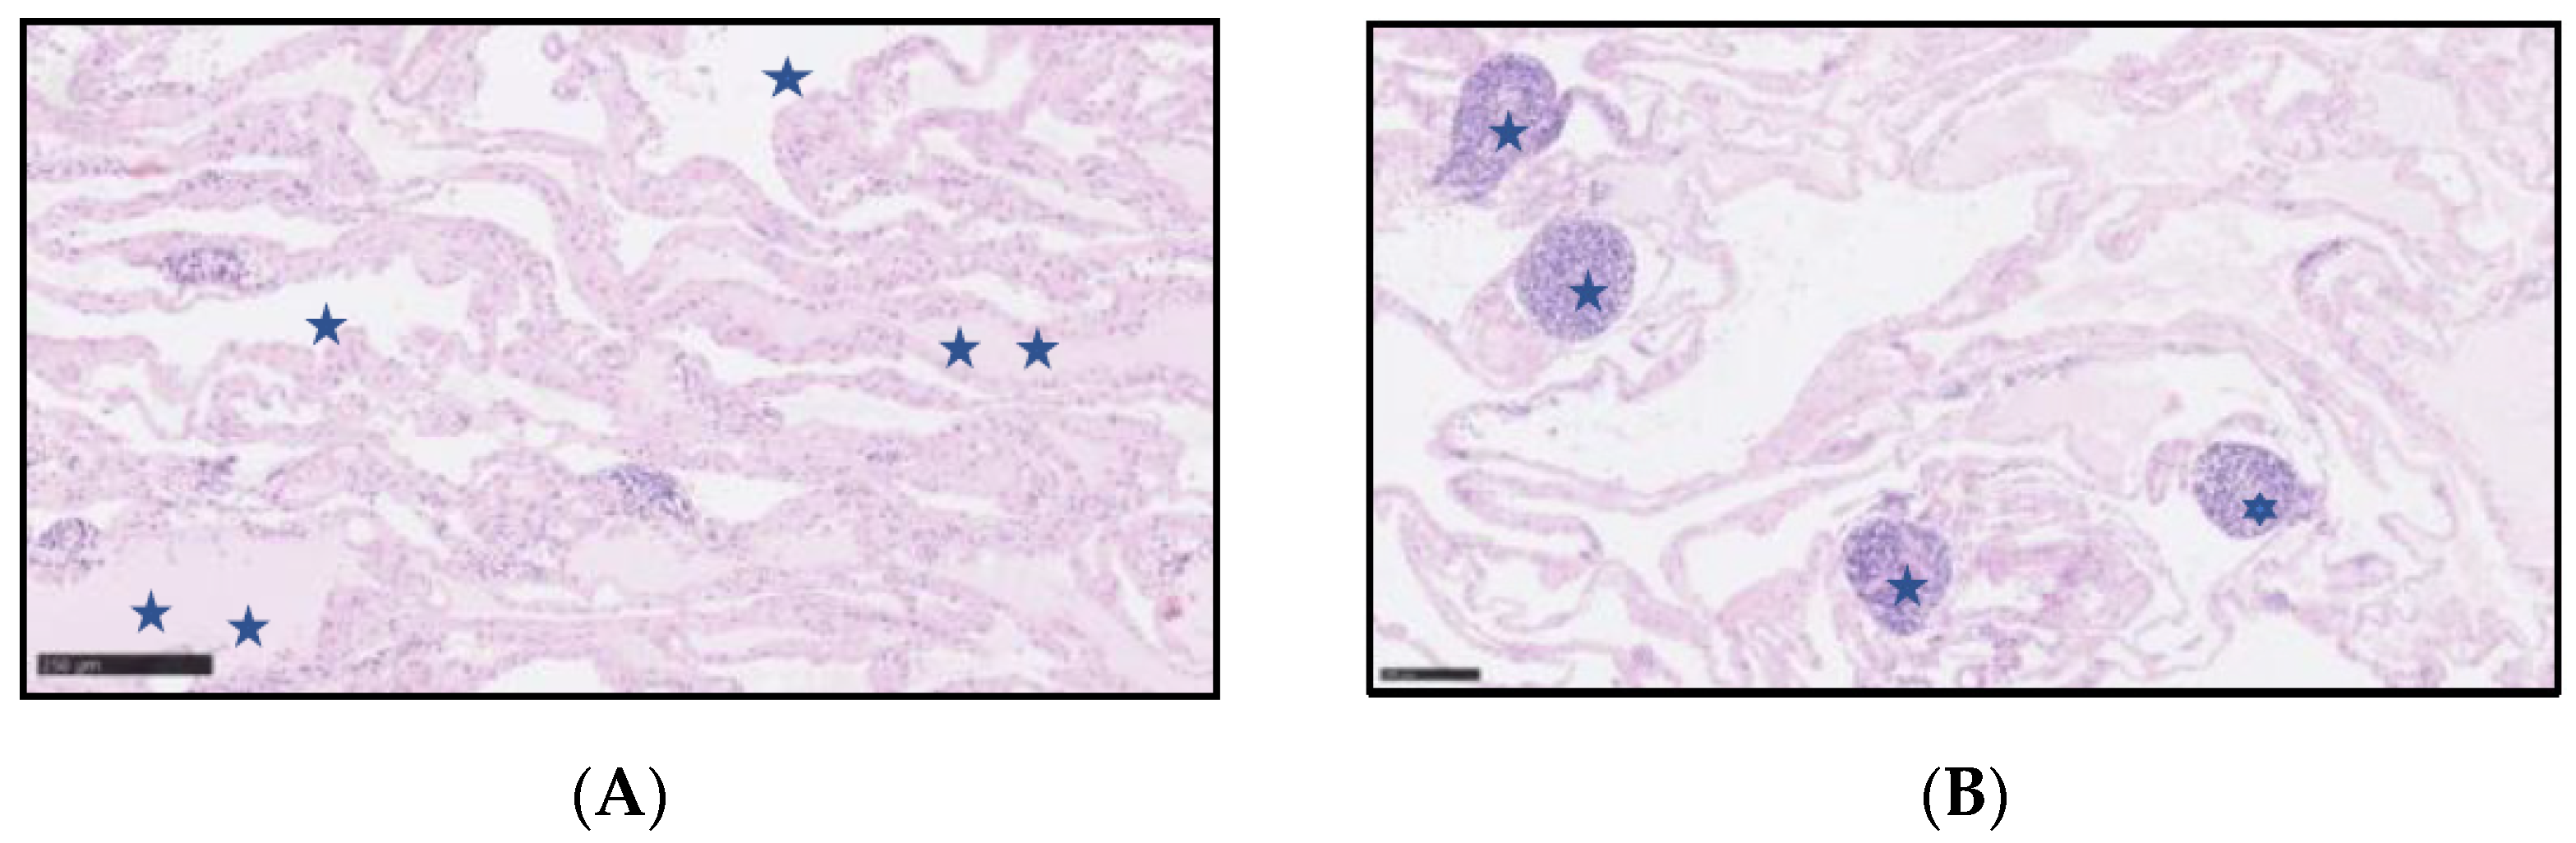

On gross examination, the resected specimen had a non-encapsulated, spongy, focally gelatinous mass measuring 7 × 5 × 2 cm. Microscopically, thin-walled, dilated vessels with different sizes, lined by a flattened endothelium without atypia (Figure 5A,B), and predominantly lymphatic in origin were observed (D2-40+, CD31+, CD34+, factor VIII+) (Figure 6A–C). Their lumina mostly contained proteinaceous fluid, with occasional admixture of lymphocytes, both B (CD20+) and T (CD3+) cells, histiocytes (CD68 KP1+), and erythrocytes, without plasma cells (CD138−, IgG4−). Larger lymphatic vessels with a layer of smooth muscle were also visible. Small lymph nodes with a preserved architecture (CD20, CD3, BCL6, CD23) and sinus dilatation were prevalent, as well as numerous smaller clusters of B and T lymphocytes (Figure 5B). Focal interstitial fibrosis and thickening of the connective tissue septum with myofibroblast proliferation were observed (SMA) (Figure 6D). The tumour focally surrounded normal blood vessels and nerve bundles and penetrated the adjacent adipose tissue, but not the stomach wall. The patient was diagnosed with a lymphangioma cavernosum.

Figure 5. (A) Lymphangioma cavernosum—Vascular spaces (one blue star), some of them with a proteinaceous fluid (two blue stars). (B). Lymphangioma cavernosum—Small clusters of lymphocytes (one blue star) within the lymphangioma. Haematoxylin and eosin staining.